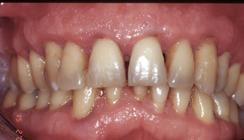

Figure 6.2.a : Parodontite chez un patient de 45 ans. De nombreux dépôts de tartre et de plaque dentaire sont visibles à la surface des dents. La gencive présente une certaine inflammation.

Figure 6.3.a : Parodontite chez un patient de 25 ans. La gencive n’est pas rétractée et seule une certaine inflammation des tissus est visible, alors que le cas est sévère.